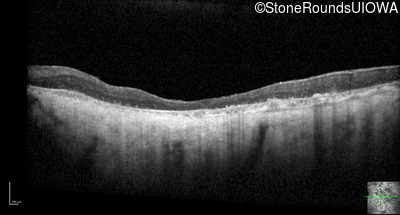

Optical Coherence Tomography - Right - Light Perception

Exemplar / OCT Stack

OCT Stack

Optical Coherence Tomography - Left - Light Perception